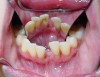

The initial periodontal evaluation included intraoral examination and a full mouth series of radiographs. These revealed severe periodontitis, localized to the lower anterior teeth (Figure 3), an unusually severe condition in an otherwise healthy young adult. Tooth No. 24 spontaneously exfoliated soon after the initial visit, as shown in the photograph taken 2 weeks after the initial visit (Figure 4). Probing depths along remaining teeth in the mandibular sextant ranged from 3 mm to 7 mm, with obvious recession and moderate to severe mobility. Plaque and calculus deposits were apparent interproximally and lingually, along with bleeding on probing. Pulp vitality was confirmed. Other areas, excluding the mandibular anterior sextant, exhibited minimal periodontitis, plaque accumulation, and marginal inflammation.

Occlusal patterns are inconsistent with the severe attachment loss around the mandibular anterior teeth. However, incisal chipping was evident on tooth No. 8 (Figure 4). Also apparent was perioral scarring, typical of intraoral piercing.

Figure 4  Buccal and lingual clinical views, second appointment.

Figure 4